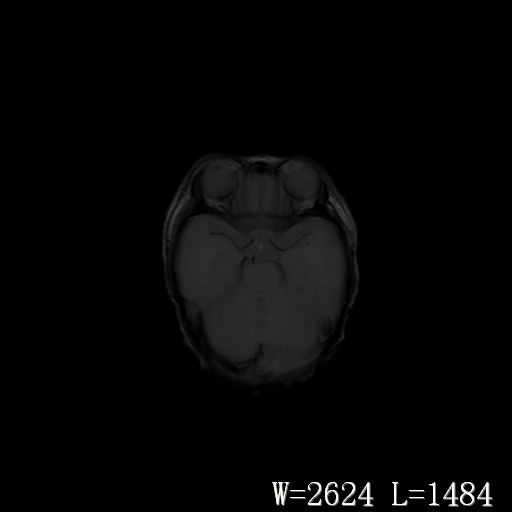

男,4天,发复抽搐1天。

脑干形态欠规则,信号增高,不知怎么解释?

脑干背侧面t1高信号是,新生儿正常已经髓鞘化好的部位